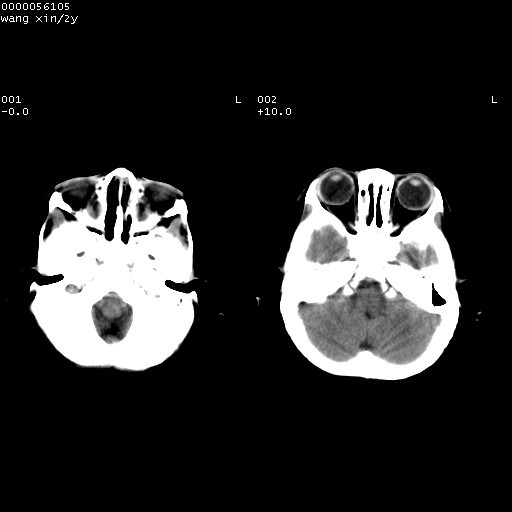

标题: PED1611:F,2Y。右侧额部小包块,光整,质硬,边界清楚,无 [打印本页]

标题: PED1611:F,2Y。右侧额部小包块,光整,质硬,边界清楚,无

右额骨内板压迫性变薄,呈椭圆形膨胀性骨吸收和低密度区,其间可见小斑片状致密影,-支持表皮样囊肿